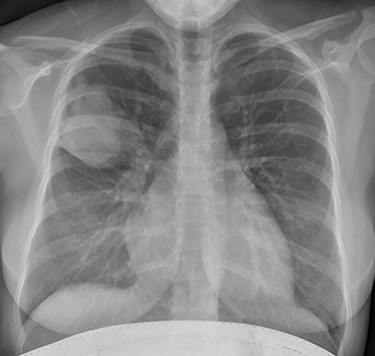

Initial investigations included a full blood panel with inflammatory markers (all within normal range) and a plain chest radiograph which demonstrated a mass in the right upper zone (Fig. 1). Computer tomography pulmonary angiogram (CTPA) scan demonstrated an 8 x 6.5 cm soft-tissue lesion within the right upper lobe (Fig. 2). This mass appeared to extend from the right hilum to the pleural surface and contained multiple small arterial branches. Her delivery date was brought forward pending further investigations. Positron emission tomography CT (PET-CT) demonstrated this lesion to be intensely fluorodeoxyglucose (FDG) avid (Fig. 3).

Plain chest radiograph demonstrating resolution of the right upper zone mass.